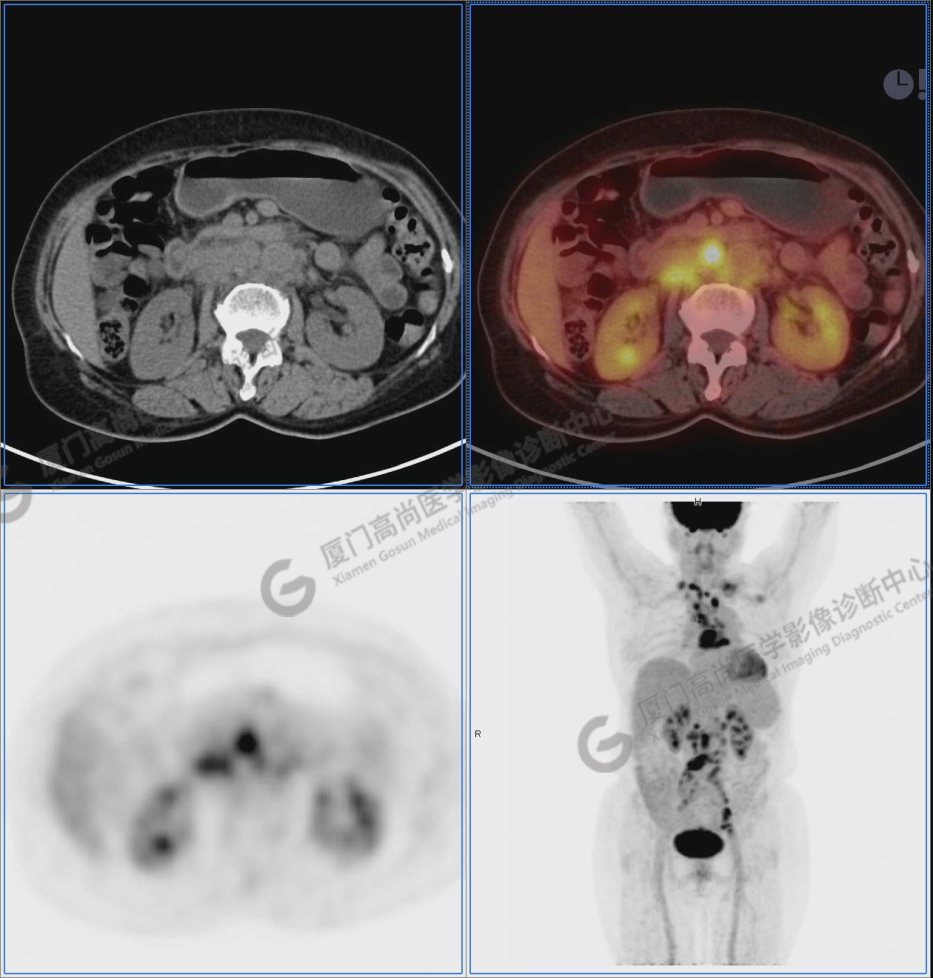

圖2-9:雙側(cè)鎖骨區(qū)、縱隔、右側(cè)內(nèi)乳區(qū)、腸系膜緣、腹膜后、雙側(cè)髂血管旁及盆腔多發(fā)腫大淋巴結(jié)影,代謝不同程度增高,考慮為轉(zhuǎn)移。

圖2

圖3

圖4

圖5